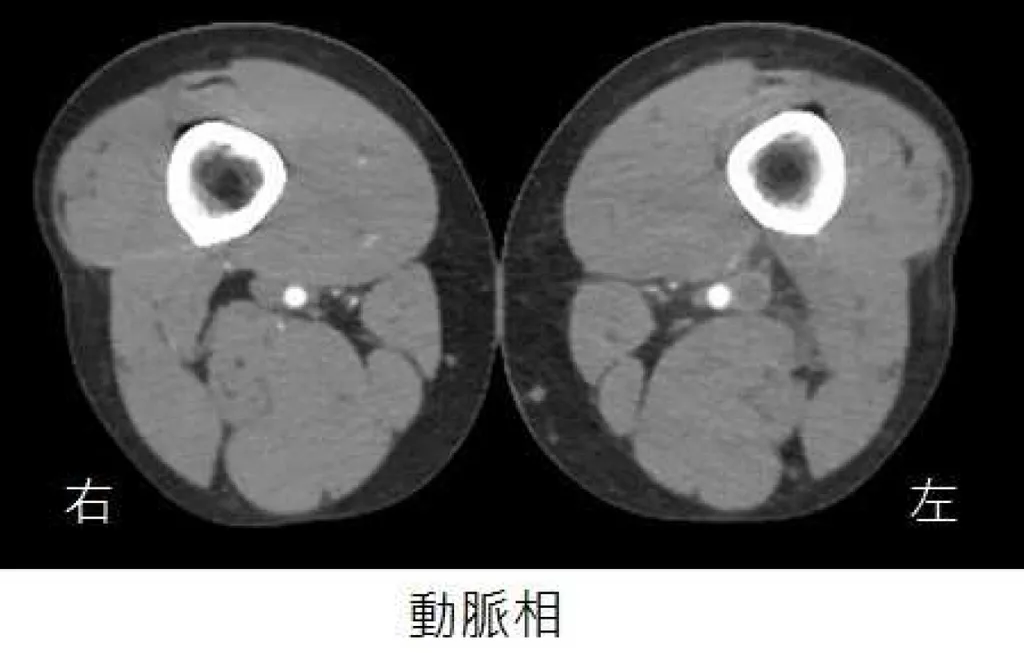

35 歲男性病人,主訴持續一星期的單側下肢腫脹,但無發燒症狀。雙側下肢靜脈注射顯影劑電腦斷層影像如圖所示,下列關於病況的敘述何者最恰當?

這題的解題核心在於從電腦斷層影像中辨識出深層靜脈栓塞(DVT),並理解其最嚴重的併發症。圖片中的靜脈相顯示左側股靜脈有顯影劑填充缺損,代表有血栓形成。